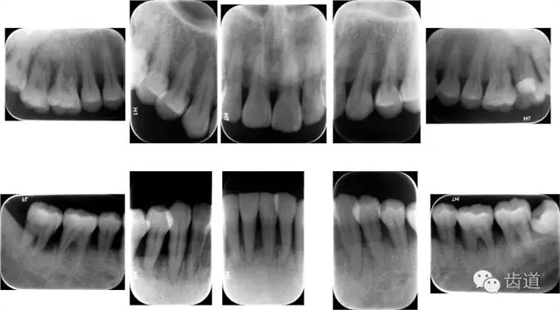

X線:根尖片、曲面斷層片(牙槽嵴頂,水平垂直吸收,程度)